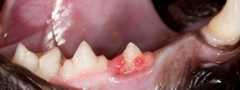

Cat's tooth with inflamed gum.A cat's tooth with a resorptive lesionDental disease is one of the most common medical conditions seen by veterinarians. More than half of all cats over the age of three have some form of dental disease.

What is tooth resorption?

Tooth resorption is the slow, progressive destruction of the tooth (crown and root), resulting in  "holes" in the affected teeth. Once sensitive parts of the tooth are exposed (dentin and pulp), these lesions become intensely painful, and the only effective and humane treatment is to extract the tooth. While the cause of this disease is unknown, poor oral hygiene can play a role in the disease process (see the handout called “Tooth Resorption in Cats” for further details).